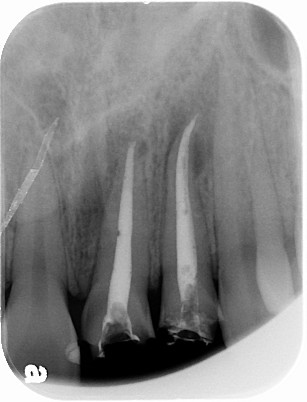

利用顯微鏡將金屬釘柱移除,再以鎳鈦超彈性器械修形根管(圖三),待患者的症狀都恢復正常後再利用熱塑型馬來膠將根管緻密封填(圖四),圖五為根管治療後的情況,與圖二相比,可見正門齒及側門齒已徹底封填。

|